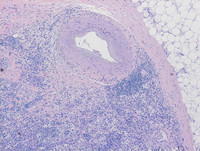

Figure 1: H&E images of breast lump

The low power images demonstrate replacement of breast parenchyma by sheets of large histiocytes and moderate intervening fibrosis admixed with dense lymphoplasmacytic infiltrate. Thick hyalinizing fibrotic band is evident at the periphery of the lesion (image to the left).

Figure 2: H&E images of breast lump

On high power photomicrographs, these infiltrating histiocytes have vesicular nuclei, abundant pale vacuolated cytoplasm and indistinct cell borders. Scattered histiocytes are notable for the presence of engulfed intact lymphocytes and red cells within the cytoplasmic vesicles (Black arrow). This process is known as ‘emperipolesis’, a microscopic hallmark of the entity. Compared to nodal RDD, extranodal RDD often demonstrates more fibrosis and a lesser degree of emperipolesis.